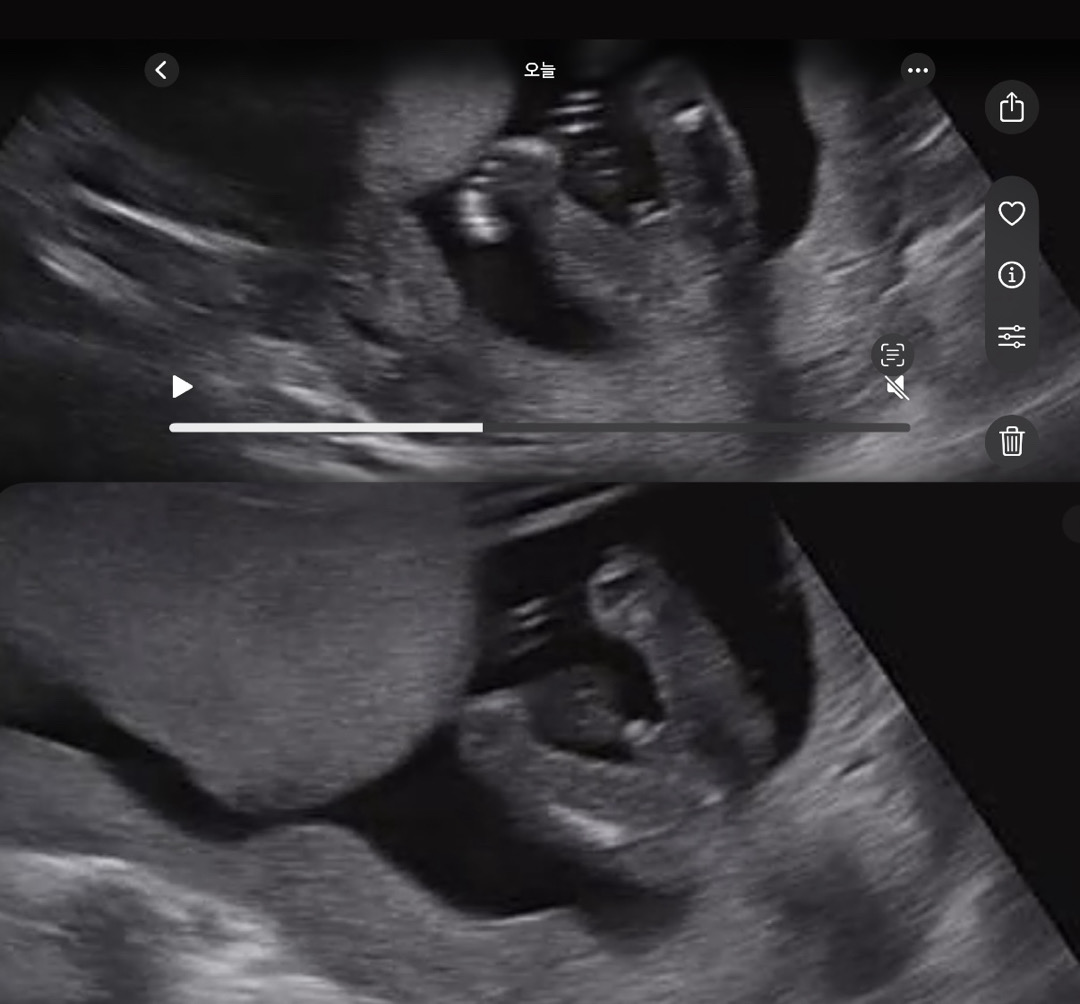

16주차 성별

아들인거 같기도 아닌거 같기도… 병원에서 확실히 대답을 안해주셔서ㅠ 성별 한번 봐주세요~

아들이용

위에 사진만 보면 딸같아요~ 아래는 딸이라면 탯줄 같아보여요ㅎ